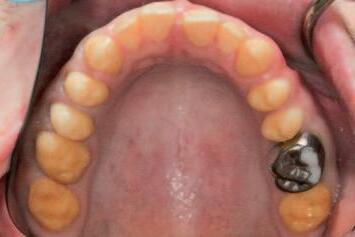

n The tooth reduction guide is tried into the mouth to confirm complete seating and to assess the extent of the anticipated interferences clinically (Figure 2).

FIGURE 2: Initial seating of the preparation guide on the dentition allows the clinician to visualise the intended outcome of this treatment step.

A C B

The external contours of the guide correspond to the planned final contours of the definitive restoration. Regions of the underlying dentition that protrude from the guide windows represent interferences, which must be selectively reduced to achieve the intended outcome. Importantly, this will act as a preliminary reduction, as an initial step prior to conventional tooth preparations for crowns.